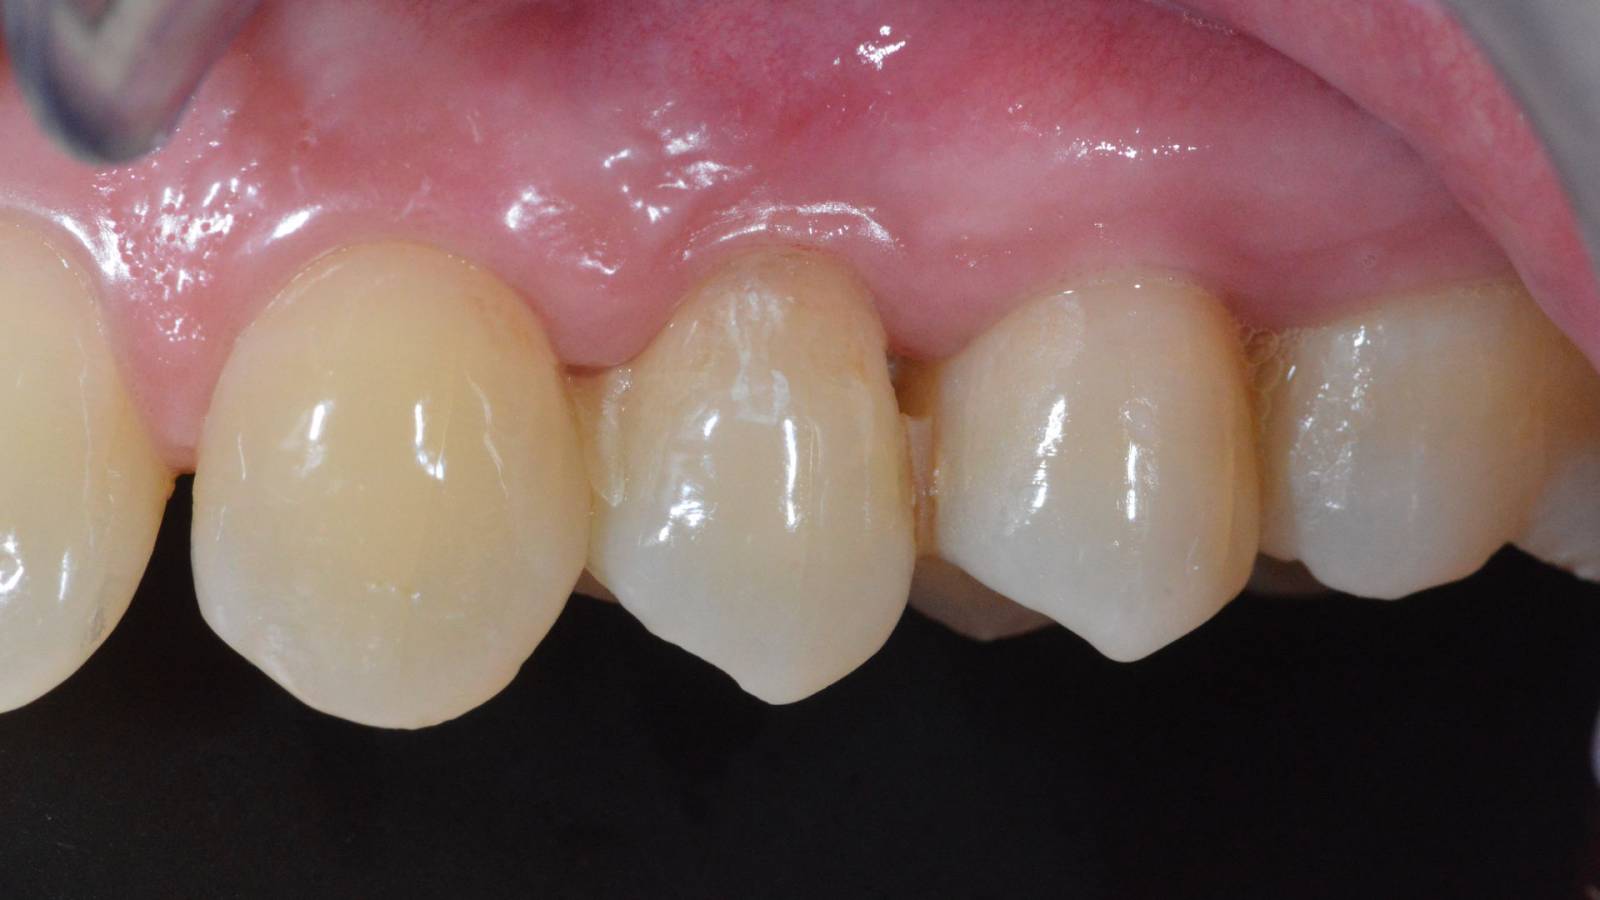

Before

Fractured ceramic restoration made from a leucite-reinforced glass-ceramic after a clinical service time of 12 years.